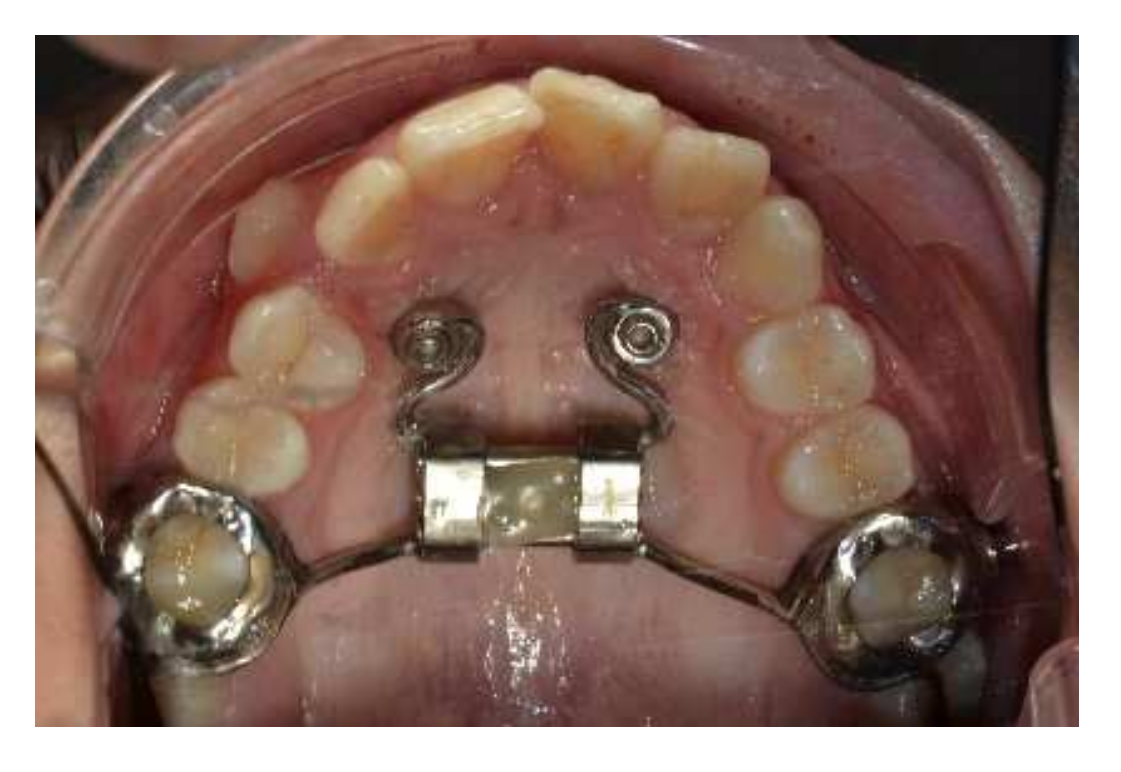

5. Treatment Progress

6. Treatment Results

7. Discussion